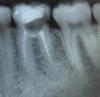

ANNA10 Опубликовано 4 июня, 2010 Поделиться Опубликовано 4 июня, 2010 (изменено) Добрый вечер!Попытаюсь описать все по порядку. В феврале, почти 4 мес назад у меня заболел зуб левая 6-ка снизу. Сделали снимок - сказали пульпит вот снимок это снимок во время лечения в первое посещениеэто снимок через 8 дней стоматолог сказал что все нормально ,только поболит 2-3 дня, и нужно поставить коронку И все это время у меня болит зуб на мои жалобы врач говорил что так и должно быть , скоро пройдетчерез месяц я сделала снимок мне сказали ждать и терпеть так как каналы запломбиоованы хорошо,а вскрывать жалко.Две недели назад распухла десна,сильная боль при малейшем надавливании на зуб врач вскрыл зуб и сказал что нашел причину поставил метапекс и мне придти через месяц ставить постоянную пломбу (если не будет болеть) Вот снимок Изменено 4 июня, 2010 пользователем ANNA10 Ссылка на комментарий

Снежана Опубликовано 4 июня, 2010 Поделиться Опубликовано 4 июня, 2010 о, добавили еще снимок, к сожалению да - удаление. Ссылка на комментарий